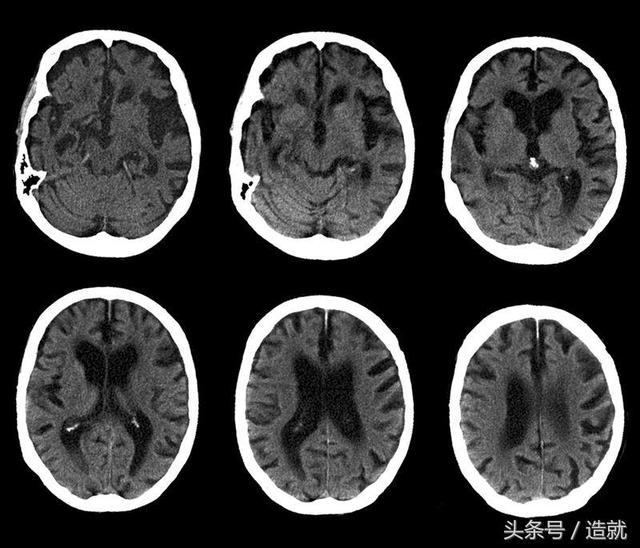

阿爾茨海默病患者腦部掃瞄圖